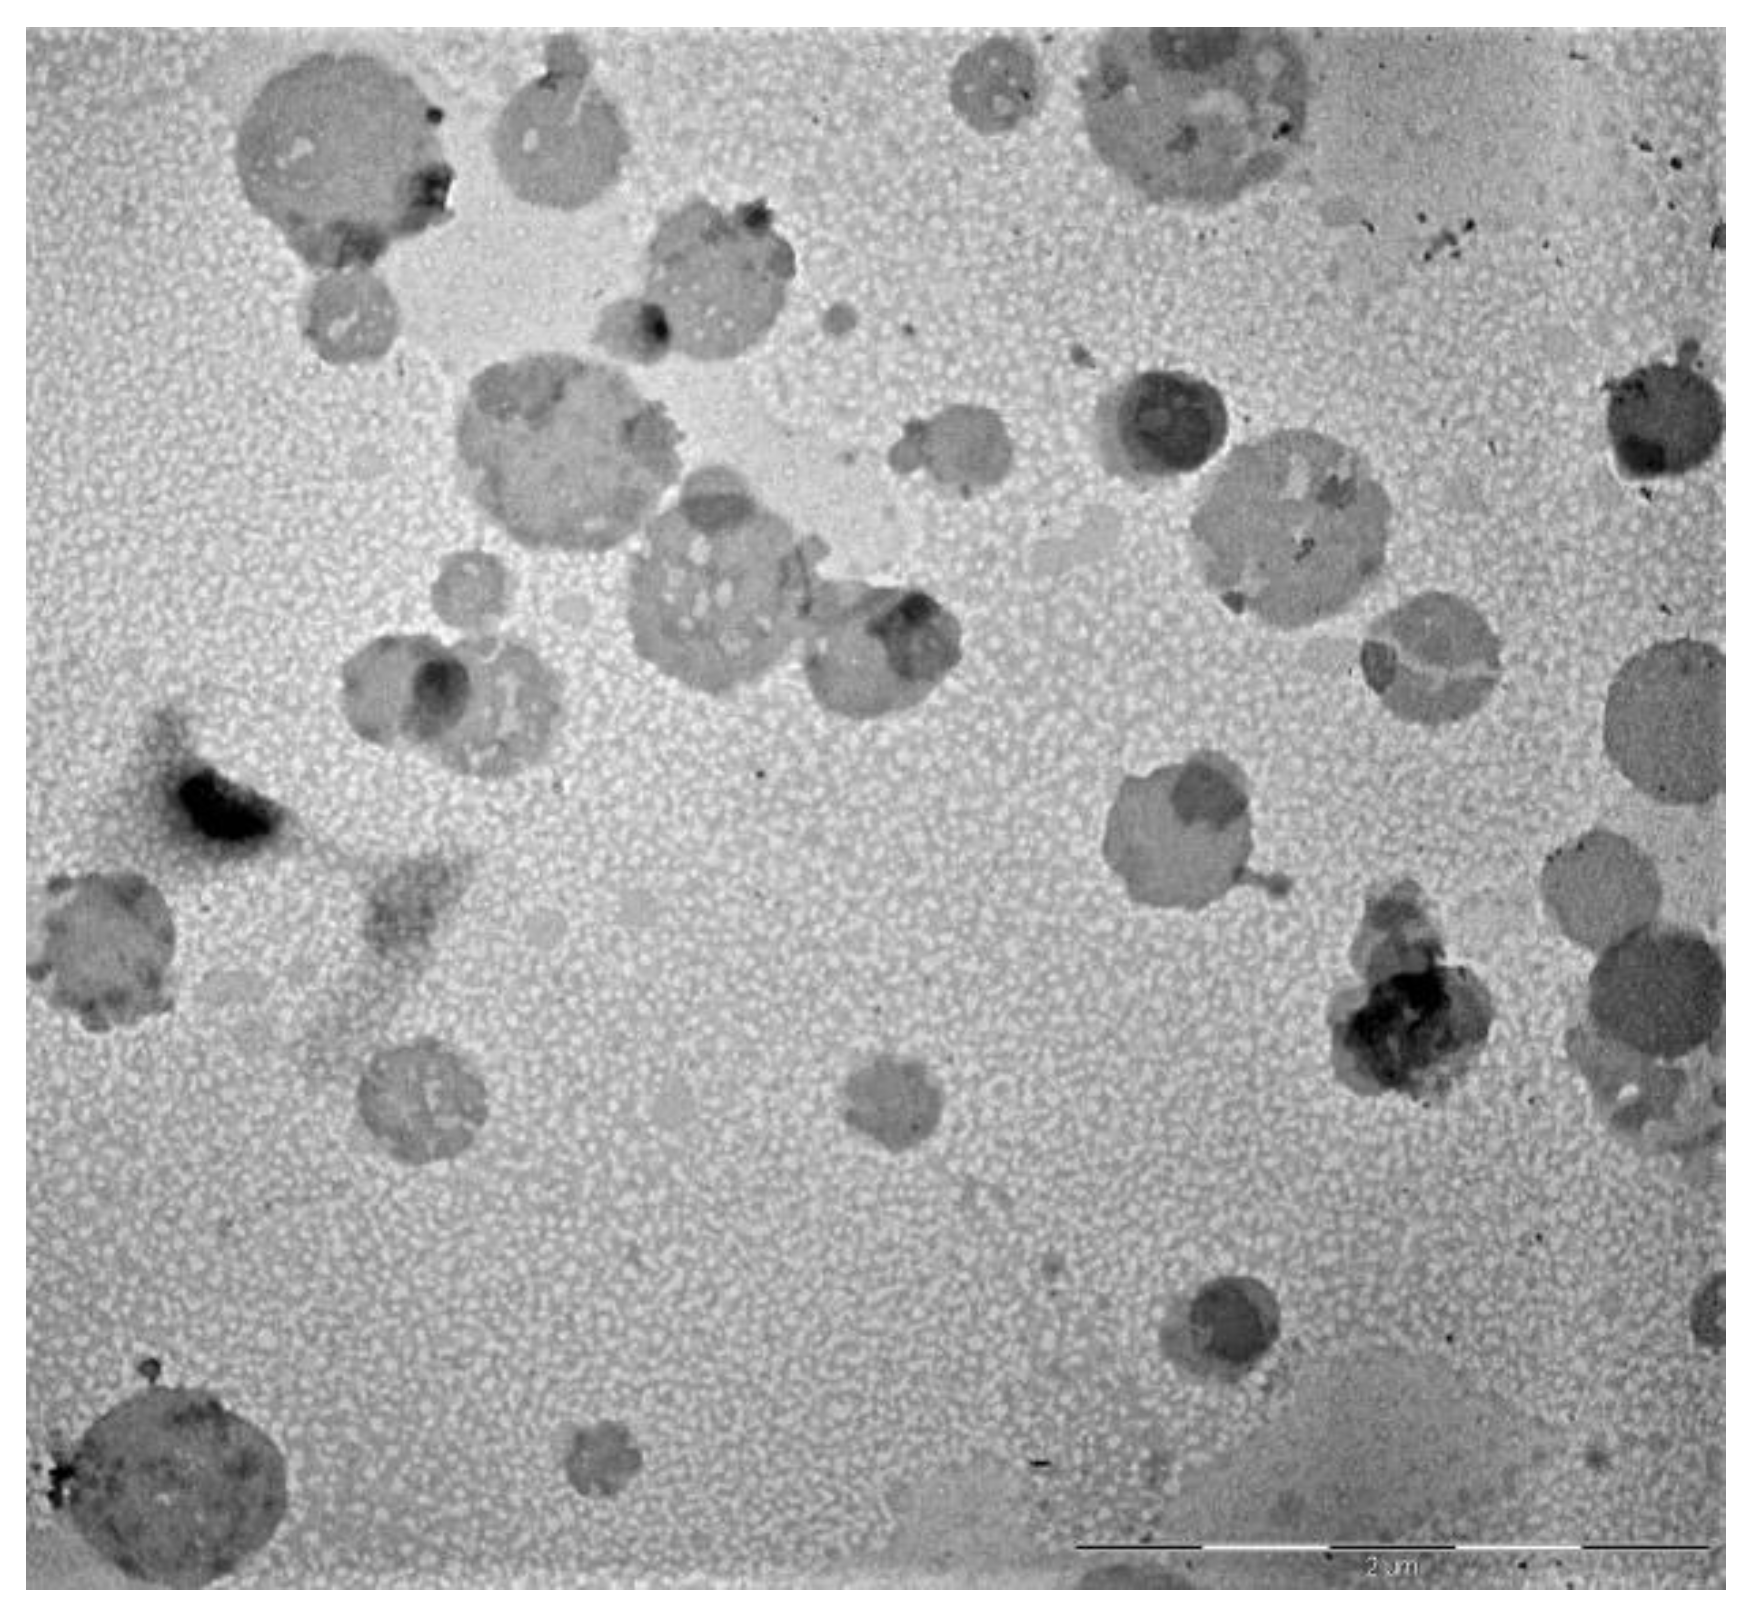

Different ratios of solid and liquid lipids and tensides were evaluated. Some tested formulations showed good physical requires for oral administration, such as size and PDI, but they were not stable. Finally, the optimized NLCs are reported in Table 2. Its composition was Stearic acid/ Brij S20 (1:2 w/w) and Capryol 90 (2:8 w/w respect to solid lipid). Brij S20 is a non-ionic tenside, derived from stearic acid covalently grafted with PEG 1000, which form a hydrophilic steric barrier around the NLCs and increase their stability [14]. This selected formulation was able to load 40 mg/mL of extract (SLM-NLCs), with an EE% of 92.4%. The presence of SLM does not influence the stability of the NLCs: when SLM were loaded into the nanoparticles, the formulation showed the same physical parameters than empty NLCs. TEM micrographs provided information on morphology and dimensions of nanoparticles: the formulation had a spherical structure with a diameter like that obtained through DLS analyses (Figure 1).

Figure 1. Transmission Electron Microscope (TEM) images of Silymarin (SLM)-NLCs.

The shape and the surface structure of NLCs were investigated by transmission electron microscope (TEM, Jeol 1010, Tokyo, Japan). The samples were opportunely diluted with distilled water, then were dropped on a 200 mesh carbon film-covered copper grid and negatively stained with phosphotungstic acid aqueous solution (1% w/v). After drying, the grid containing the sample was observed with the TEM [14].